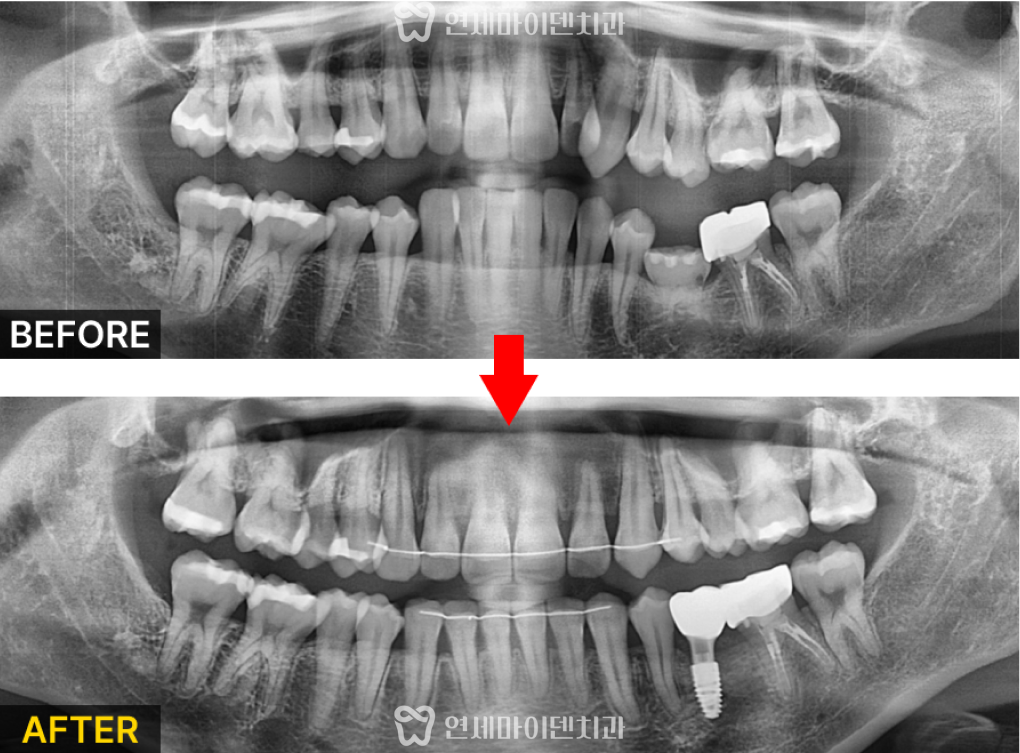

방사선 촬영 결과, 유치 아래에는

영구치가 존재하지 않는 결손 상태였습니다.

위쪽 송곳니는 제자리를 벗어나

안쪽으로 매복되어 배열을 어지럽히고 있는 상태였습니다.

전체적으로 어금니는 뒤로 기울어 있고,

앞니는 올라간 형태로 교합의 높낮이가 불균형했으며,

얼굴 비율상 수직 길이도 짧아 보였습니다.

유치가 있던 부위는 발치 후 골 이식을 진행했고

교정치료 기간동안 공간을 확보한 뒤

임플란트를 식립하기로 했습니다.

최종적으로 안쪽에 숨어있던 송곳니가 정상 배열을 이루고,

유치 부위에는 임플란트가 정확히 식립되어

기능적·심미적으로 모두 회복되었습니다.